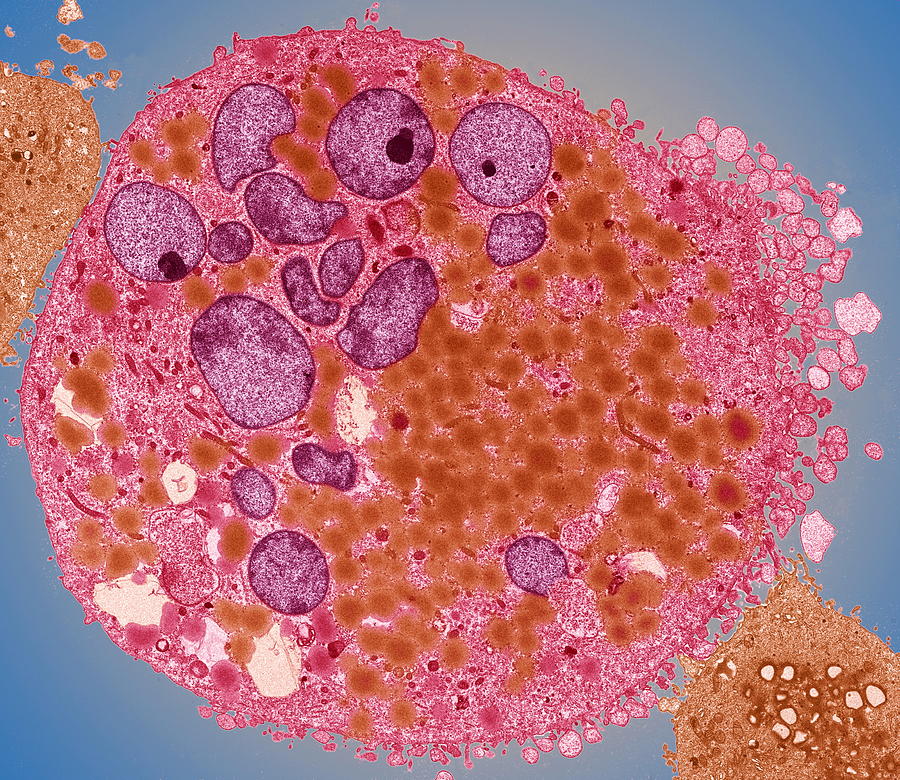

Bladder Cancer Photograph by Zephyr/science Photo Library – Pixels

Bladder Cancer Cell Photograph by Steve Gschmeissner/science Photo Library

Bladder Cancer Cell, Tem Photograph by Steve Gschmeissner